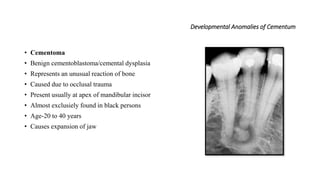

• Cementoma

• Benign cementoblastoma/cemental dysplasia

• Represents an unusual reaction of bone

• Caused due to occlusal trauma

• Present usually at apex of mandibular incisor

• Almost exclusiely found in black persons

• Age-20 to 40 years

• Causes expansion of jaw